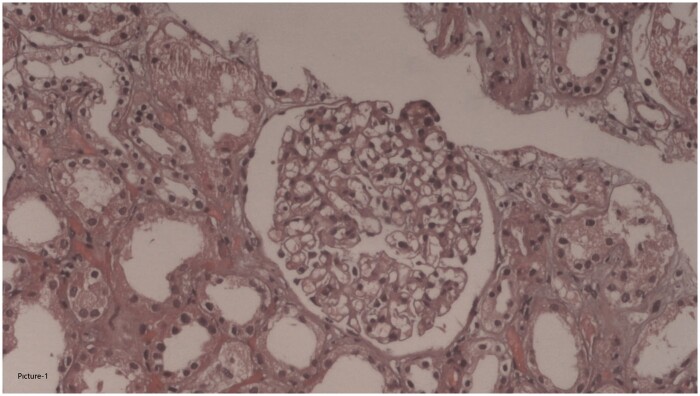

No retinopathy findings were detected in the fundus examination. A kidney biopsy performed on 17 March 2021 contained 45 glomeruli; one was globally sclerotic. The rest were of normal size and cellular structure. Interstitial inflammation, fibrosis or tubular atrophy were not observed. Vascular structures were normal. No amyloid deposition was detected in the Congo red staining. No evidence of immunoglobulin A (IgA), IgM, IgG, C3, C1q, fibrinogen, kappa light chain or lambda light chain deposition was found in eight glomeruli by immunofluorescence. Thus, the biopsy was consistent with minimal change glomerulopathy (Figure 1).

FIGURE 3:

Normal histological appearance of glomerulus seen in first renal biopsy. Normal interstitial area is also discernible (haematoxylen & eosin, ×200).